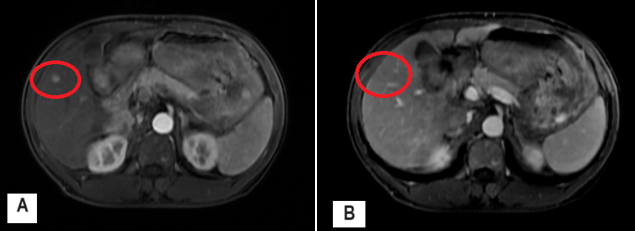

- Siêu âm ổ bụng:

Nhu mô gan thô, hạ phân thùy V có nốt giảm âm kích thước 1,1x0,8mm

Hình 1: Hình ảnh siêu âm gan: có nốt giảm âm hạ phân thùy V (mũi tên đỏ)